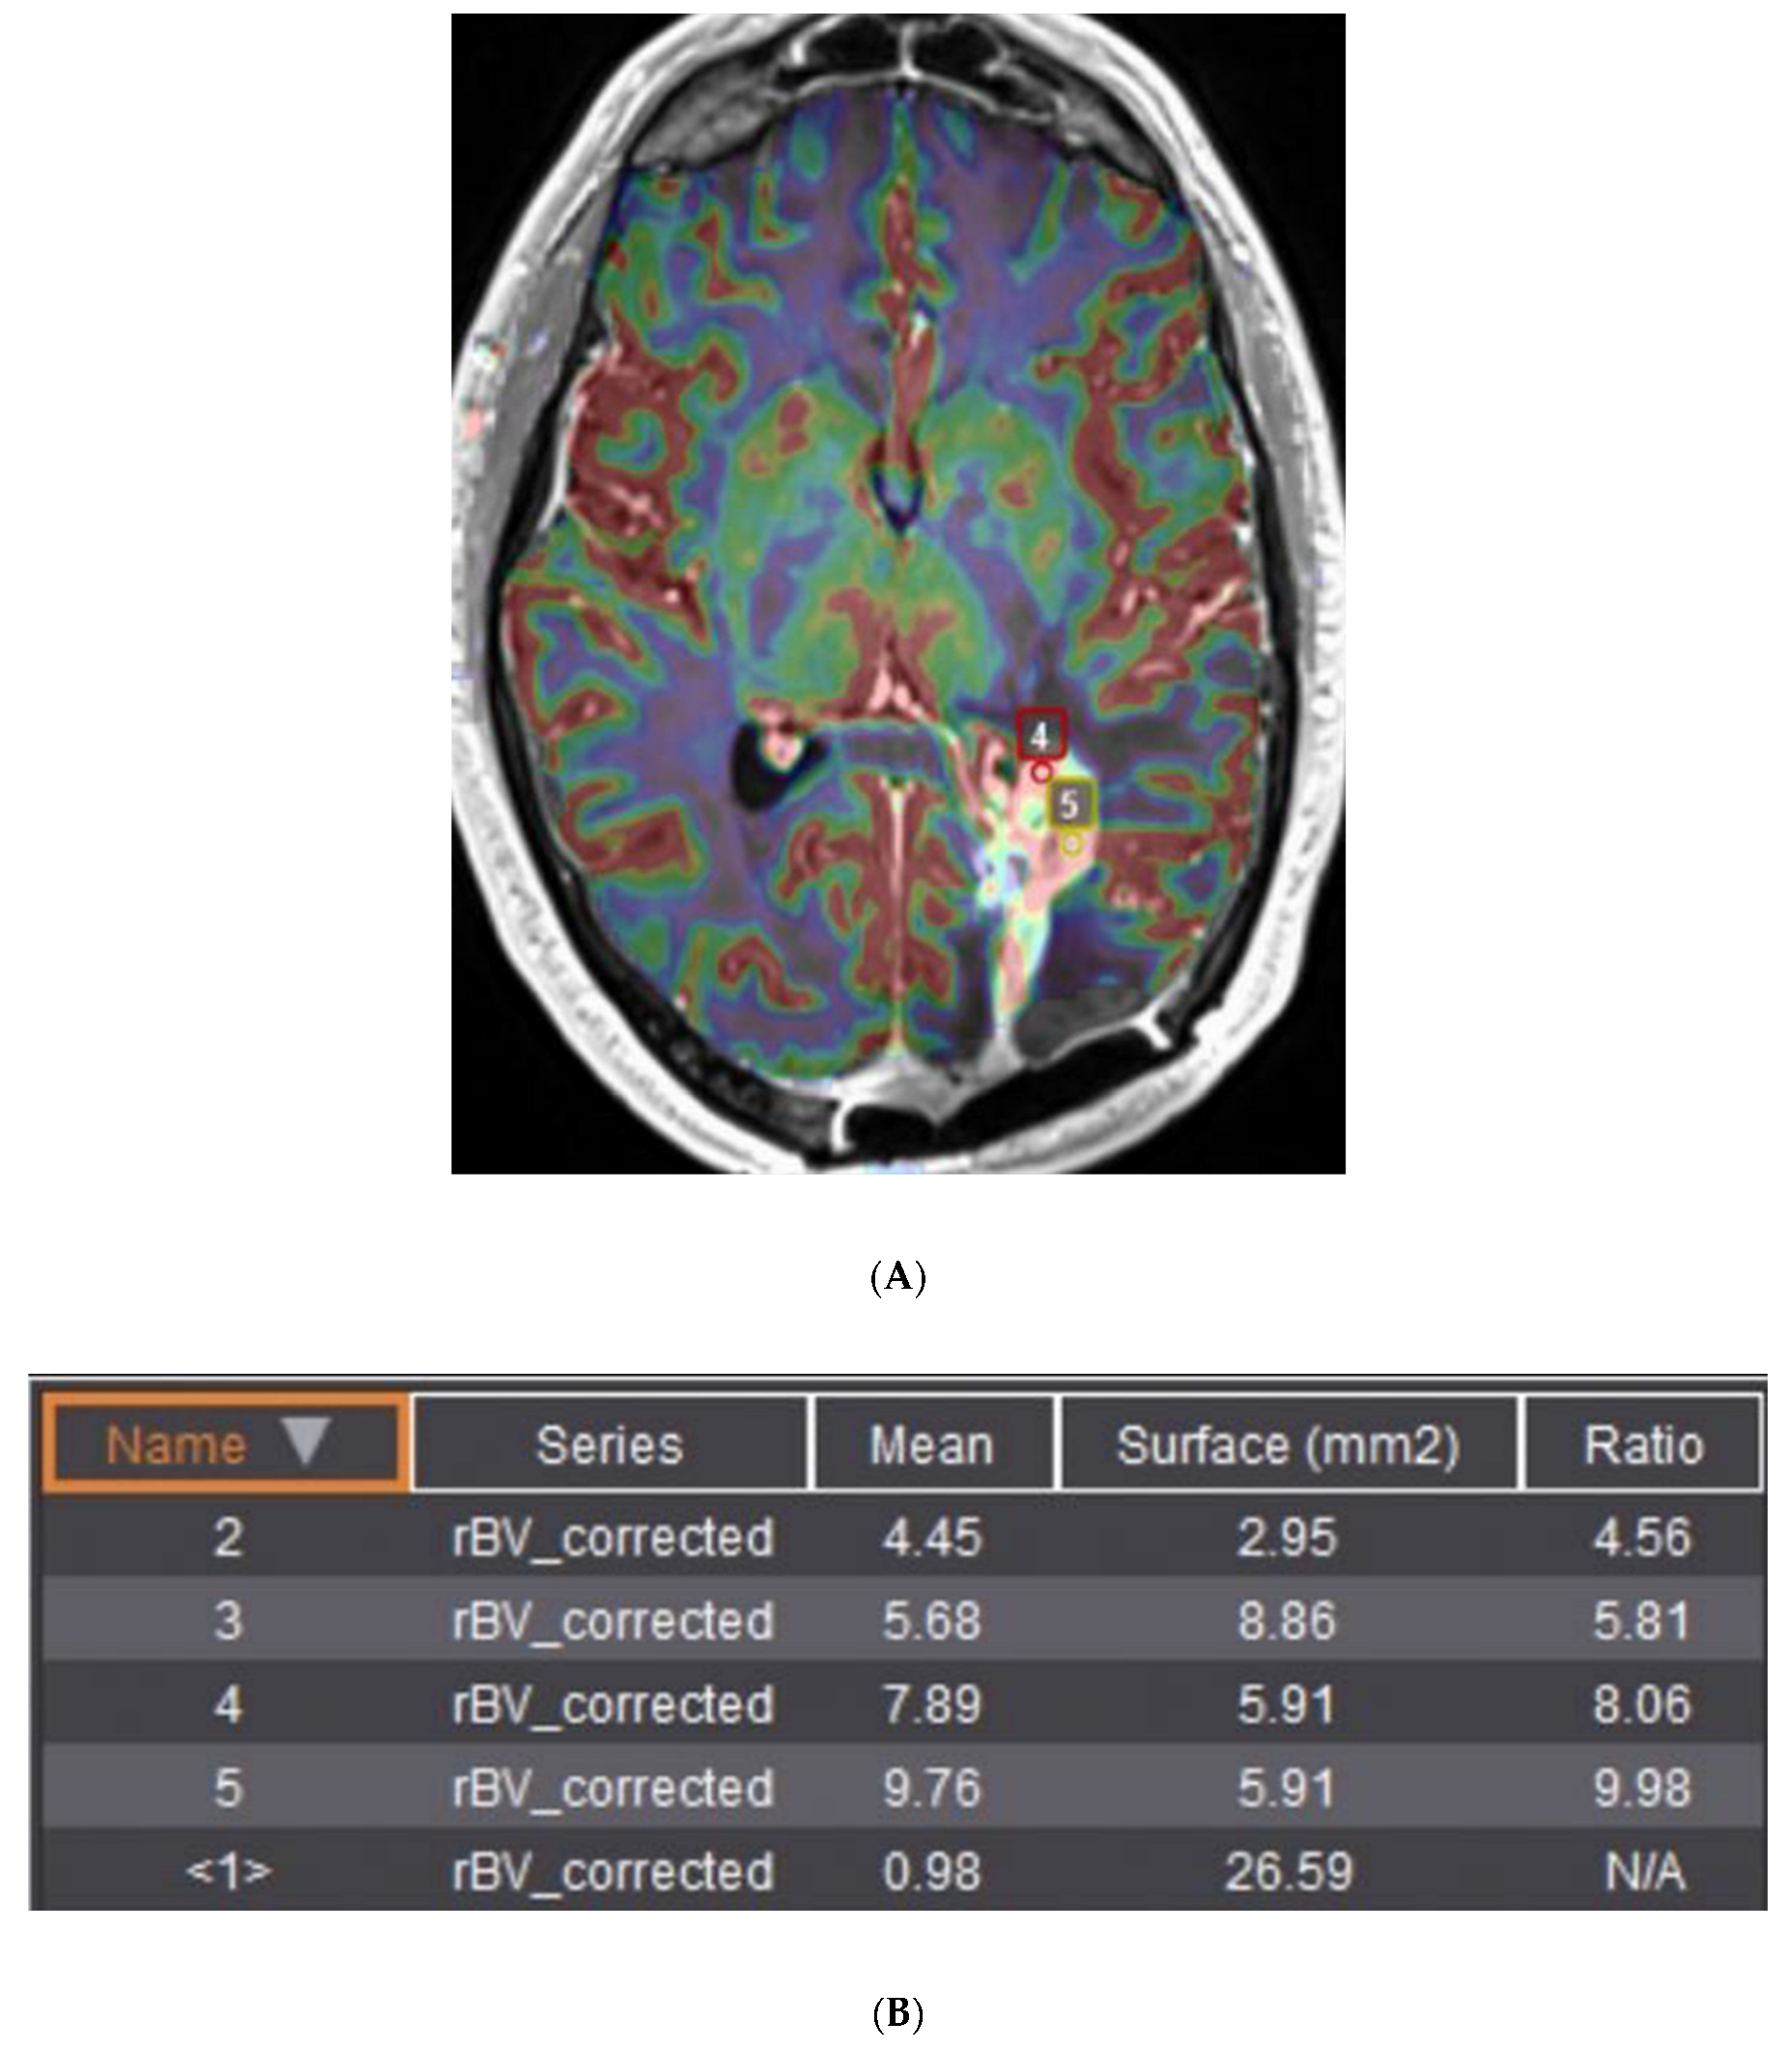

8. Progression of Disease versus Treatment Effect

- Gahramanov, S.; Raslan, A.M.; Muldoon, L.L.; Hamilton, B.E.; Rooney, W.D.; Varallyay, C.G.; Njus, J.M.; Haluska, M.; Neuwelt, E.A. Potential for differentiation of pseudoprogression from true tumor progression with dynamic susceptibility-weighted contrast-enhanced magnetic resonance imaging using ferumoxytol vs. gadoteridol: A pilot study. Int. J. Radiat. Oncol. Biol. Phys. 2011, 79, 514–523. [Google Scholar] [CrossRef] [PubMed]

- Henriksen, O.M.; Del Mar Alvarez-Torres, M.; Figueiredo, P.; Hangel, G.; Keil, V.C.; Nechifor, R.E.; Riemer, F.; Schmainda, K.M.; Warnert, E.A.H.; Wiegers, E.C.; et al. High-Grade Glioma Treatment Response Monitoring Biomarkers: A Position Statement on the Evidence Supporting the Use of Advanced MRI Techniques in the Clinic, and the Latest Bench-to-Bedside Developments. Part 1: Perfusion and Diffusion Techniques. Front. Oncol. 2022, 12, 810263. [Google Scholar] [CrossRef] [PubMed]

- Jones, K.K.; Maziero, D.; Ford, J.C.; Stoyanova, R.; Goryawala, M.; Diwanji, T.; Mellon, E.A. MRI-guided radiotherapy identifies early pseudoprogression of glioblastoma. Res. Sq. 2020. [Google Scholar] [CrossRef]